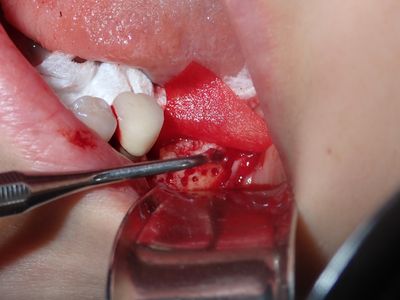

TZeng - vertical bone graft

large crestal defect from previous perio infection, site prepared with small little osteotomies and grafted with sticky bone from allograft/20% xeno, collagen membrane soaked in prf fluid tacked with three membrane tacks, additional fibrin membrane placed.